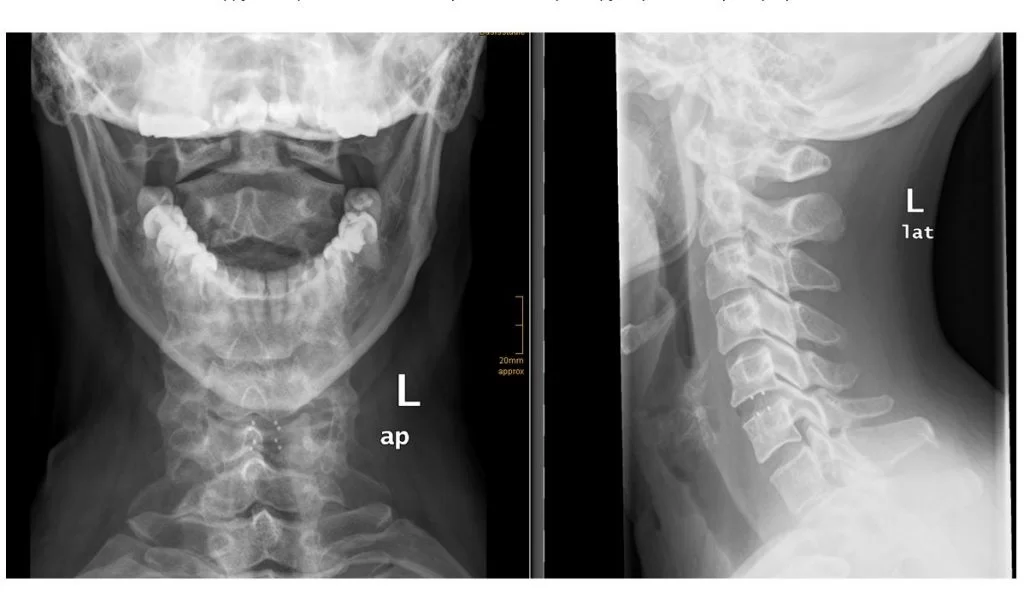

Η πρόσθια αυχενική δισκεκτομή γίνεται σε ασθενείς που έχουν δισκοκήλη/προβολή δίσκου ή/και οστεόφυτα στην αυχενική μοίρα της σπονδυλικής στήλης και ως εκ’ τούτου έχουν πόνο στον αυχένα και στα άνω άκρα.

Ο εκφυλισμός του δίσκου και των σπονδύλων (οστεόφυτα) μπορεί να επηρεάσουν το διαθέσιμο χώρο για το νωτιαίο μυελό και τα νεύρα. Ως αποτέλεσμα, ο νωτιαίος μυελός και τα νεύρα ενδέχεται να συμπιεστούν ή και να τραυματιστούν.

Βέβαια, προτού φθάσει ένας ασθενής στη χειρουργική επέμβαση, θα πρέπει να έχουν εξαντληθεί και να έχουν αποτύχει συντηρητικά μέτρα, όπως φάρμακα, ανάπαυση και φυσικοθεραπεία. Επίσης, το χειρουργείο έχει σαφή ένδειξη όταν υπάρχει νευρολογική βλάβη και μυελοπάθεια.